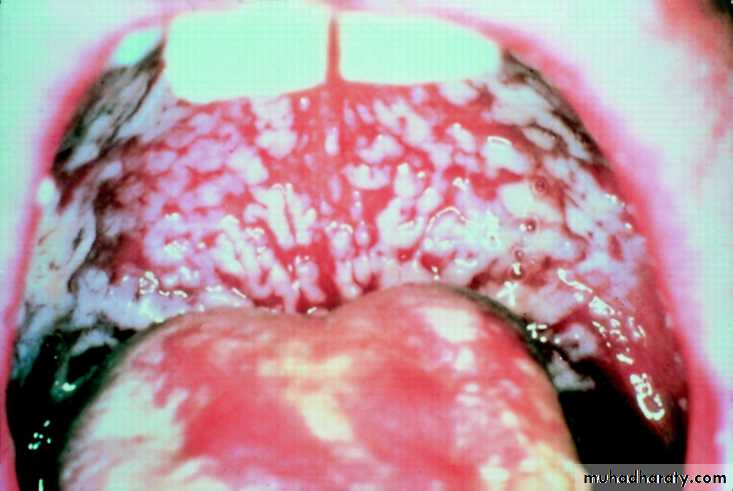

Oral candidiasis ( thrush)

White coated tongue due to candidiasis occur when there is low immunity due to HIV , diabetes , malignancy , steroid use , prolonged antibiotic therapy .Should be differentiated from food sticking on the tongue !